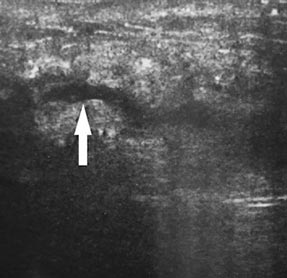

Наглядно ультразвуковая картина послеоперационных ран представлена на рис. 1–5. Показана положительная динамика разрешения полостных образований послеоперационной раны на 3-и, 5-е и 7-е сутки. Переход гипоэхогенной зоны в сторону уменьшения и появления участков гиперэхогенной структуры на 7-е сутки послеоперационного периода свидетельствует об уменьшении воспалительных процессов, снижении риска увеличения полостных образований и формировании фазы регенерации.

Рис. 2. Ультразвуковая картина передней брюшной стенки живота того же больного (см. рис. 1) на 5-е сутки после лапаротомии. Гипоэхогенная зона в области апоневроза белой линии живота по сравнению с 3-м днём наблюдения уменьшилась до 6 мм